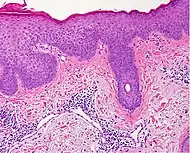

| Lichen planus | Irregular epidermal hyperplasia with a jagged “sawtooth” appearance, compact hyperkeratosis or orthokeratosis, foci of wedge-shaped hypergranulosis, basilar vacuolar degeneration, slight spongiosis in the spinous layer, and squamatization. The dermal papillae between the elongated rete ridges are frequently dome shaped. Necrotic keratinocytes can be observed in the basal layer of the epidermis and at the dermal-epidermal junction. Eosinophilic remnants of anucleate apoptotic basal cells may also be found in the dermis and are referred to as “colloid or civatte bodies”. Whickham striae are usually seen in the areas of hypergranulosis. Vacuolar degeneration at the basal layer may be noted leading to focal subepidermal clefts (Max Joseph spaces). Squamatization occurs as a result of maturation and flattening of cells in the basal layer. It happens in areas of marked hypergranulosis with prominence of the sawtooth pattern of rete ridges. Wedge-shaped hypergranulosis can occur in the eccrine ducts (acrosyringia) or hair follicles (acrotrichia). In the hypertrophic subtype, the associated hyperkeratosis, parakeratosis, hypergranulosis, papillomatosis, acanthosis, and hyperplasia markedly increased with thicker collagen bundles forming in the dermis. Moreover, the rete ridges are more elongated and rounded as opposed to the typical sawtooth pattern. In atrophic LP, loss of the rete ridges and dermal fibrosis is prominent. In vesiculobullous LP, the disease progression is quicker. Hence, some of the distinctive features such as hyperkeratosis, hypergranulosis, or dense lymphocytic dermal-epidermal infiltrate may not be present. LP lesion may resolve with residual hyperpigmentation caused by a persistent increase in the number of melanophages in the papillary dermis.[9] | ![]() | ![]() |